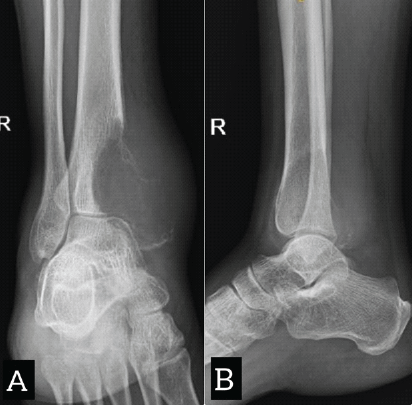

A Rare Case Report of Giant Cell Tumor in the Distal Tibia: Management with Tumor Excision and Limb Reconstruction with Ilizarov Fixator

V Harish Arvind , K Tarun Prashanth , M R Thirunthaiyan , R Dorai Kumar , B Sundararaja

………………………………p.111-115